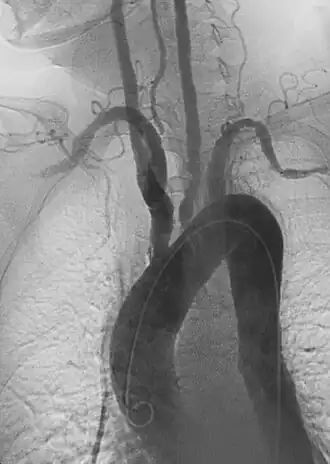

| Angiografia anterior de aorta e grandes vasos com estenose. | |

Durante o exame físico uma diferença entre os pulsos radiais esquerda e direita podem ser percebidos, geralmente um dos pulsos está ausente e o outro aumentado. A estenose dos ramos da aorta afetados pode ser auscultada. Estudos de imagem (como ressonância magnética, raios-X e angiogramas), que mostram a localização e a gravidade da inflamação e aneurismas nas artérias.[5]